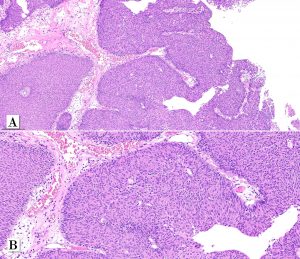

A male patient in his early 70s underwent surgical removal a single pedunculated 3 cm polypoid tumor in the bladder mucosa at the left lateral wall.

Papillary urothelial carcinoma, noninvasive, whorled subtype

Divergent differentiation and subtypes of invasive urothelial carcinoma should be mentioned in pathology reports and quantified. Morphologic variations within noninvasive papillary urothelial carcinoma are more commonly overlooked and has no known prognostic implications to date.

One rare morphologic subtype of in noninvasive papillary urothelial carcinoma has been described as a whorled pattern. Patriarca et al. 2014 described a series of 12 patients: all noninvasive and most of them 11/12 classified as low-grade. One patient had a tumor with mixed grade (5% of the tumor at other areas. Whorled pattern shows concentrically organized cell structures, without morphological evidence of keratinization, similar to the whorling structures of transitional meningioma.

In that series, none of the cases experienced T1 stage progression and two recurrences occurred. One of the recurrent tumors was the one harboring small focus of high-grade tumor inside the primary lesion. Interestingly, the recurrent cases maintained the same whorling pattern in the second transurethral resection specimens. Therefore, although limited data on follow up is available, clinical behavior seems to be similar to low-grade noninvasive papillary urothelial carcinoma (Patriarca et al. 2014). Awareness of this morphologic subtype is important to avoid misclassification of other epithelial lesions which may show squamous or squamoid morphology.